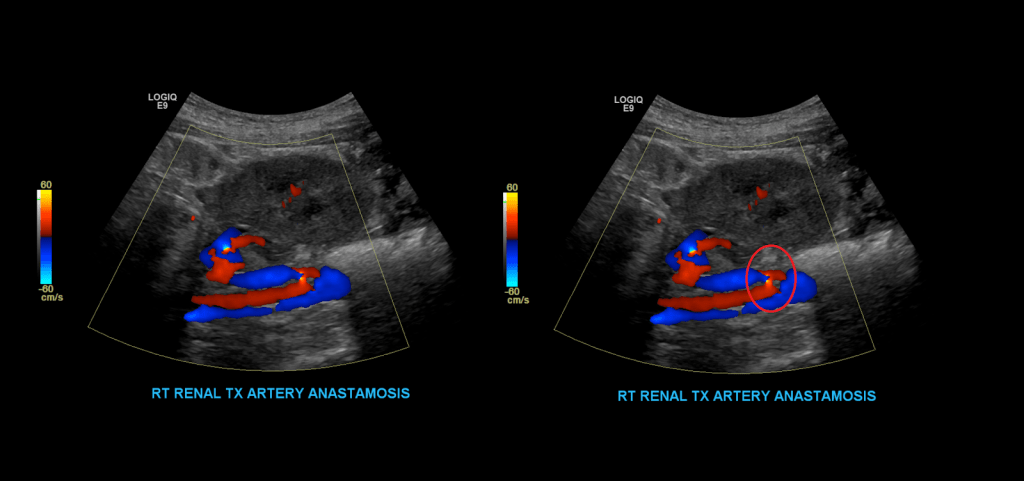

Proceed to doppler the transplant main renal artery and vein. Given the tortuosity sometimes seen in the donor arteries, measuring velocities with angle correction can be tricky. My rule of thumb is that if the artery is perpendicular to the transducer face I don’t use angle correction. If it is parallel to the transducer face I do use angle correction.

Measure the peak systolic and end diastolic velocity. Resistive Index is normally between 0.50 and 0.70. The waveform should be a low resistance waveform with forward flow throughout the cardiac cycle. Take Doppler samples at the anastomosis/proximal section (pay close attention here look for aliasing to detect anastomotic stenosis), the mid and distal portions as well. If there’s any aliasing along the vessel take spectral Doppler samples there too.